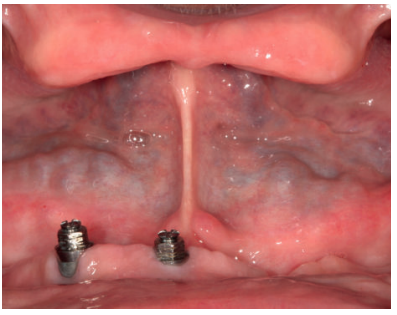

Presentamos el caso de una mujer de 67 años que acude a la consulta para solicitar un tratamiento que mejore la estética y la funcionalidad de las prótesis removibles que porta. En la radiografía panorámica inicial se observan dos implantes en la región anterior mandibular que actualmente no están formando parte de la rehabilitación, que en algún momento sostuvieron una barra para una sobredentadura (Figura 2). En la imagen de sonrisa e intraoral podemos ver la prótesis removible superior e inferior deteriorada y con zonas fracturadas (incisivo central superior derecho) (Figura 3). Al retirar las prótesis podemos observar los implantes con dos tornillos fracturados en su interior (Figura 4).